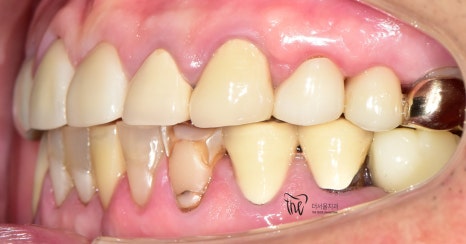

우선 교합면에서 바라보게 되면,

곳곳에 치아 결손 부위가 관찰이 되는데

이가 빠진지 시간이 꽤나 오래 되셨다는 것을

한 눈에 알아차릴 수 있습니다.

바로 결손부위를 보게 되면, 골 폭이 상당히

좁아져 있는 것을 볼 수 있는데 이는 치아 상실 후

방치 된 시간이 꽤나 오래 되었다는 것에 따른

반증이기 때문입니다.

일단 사진에서 볼 수 있는 범위까지는,

한국에 계신 기간동안 열심히 치료해서

많은 변화를 안겨다 드렸었습니다.